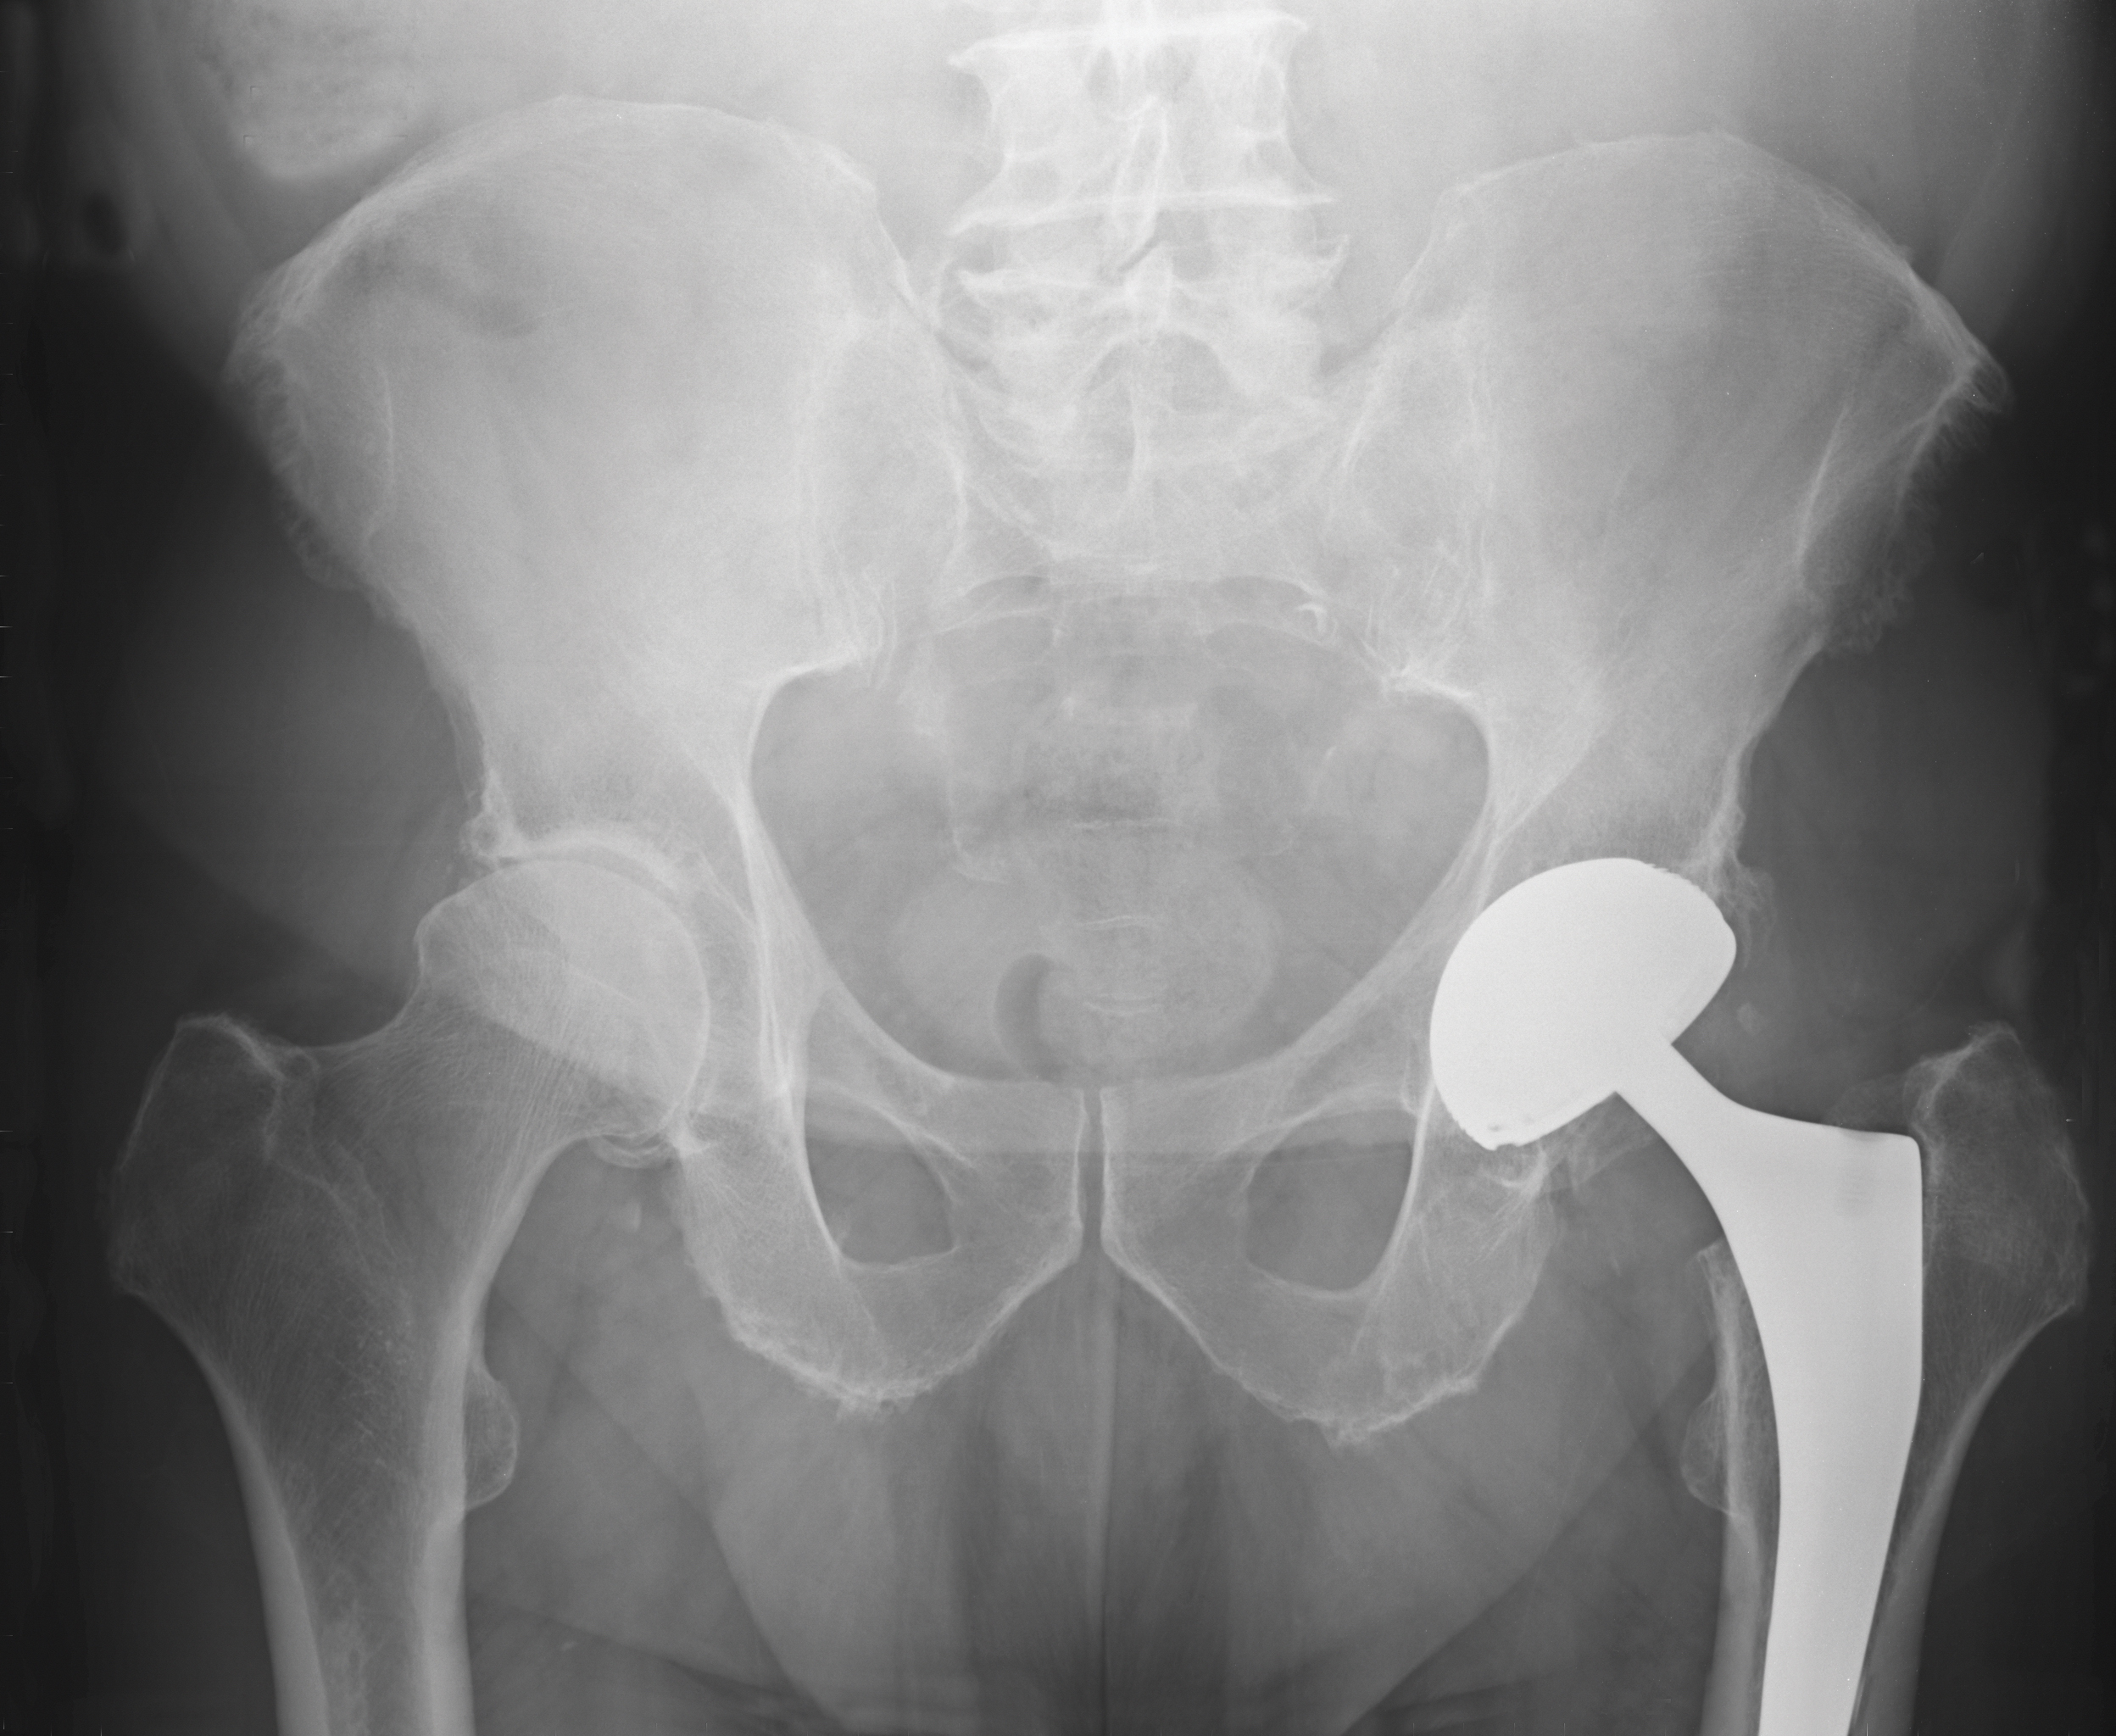

Innsetting av sementerte proteser hos eldre med underliggende sykdommer og lårhalsbrudd har gitt flere uønskede effekter. På tide å justere praksis?

Plastmaterialet polymetylmetakrylat ble tatt i bruk for nesten hundre år siden innen tannmedisinen. I mellomkrigstiden ble materialet formet til proteser og satt inn i ødelagte hofteledd. Disse implantatene smuldret opp og ble forsøkt erstattet av metallproteser. Disse destruerte benet og løsnet (1, 2).

Metallproteser var ingen suksess inntil en engelsk kirurg, sir John Charnley, i perioden 1950–60 utviklet en teknikk der akrylsement ble sprøytet ned i benmargen før den polymeriserte og derved støpte fast protesen. Pasienten kunne da bevege seg uten smerter (3). Dette ble en stor suksess og starten på en ny æra for behandling av sykdom og skade i hofteleddet.

Innsetting av usementerte proteser er ikke assosiert med de samme alvorlige perioperative komplikasjonene som sementerte implantater (6–8). Imidlertid har innsetting av usementerte proteser vært assosiert med periprotetiske frakturer, tidlig løsning og reoperasjoner (9). Norsk hoftefrakturregister har derfor valgt å anbefale bruk av sementerte proteser til alle pasienter med lårhalsbrudd over 70 år (10, 11). Tilsvarende konsensusanbefaling kommer fra NICE i England (12).